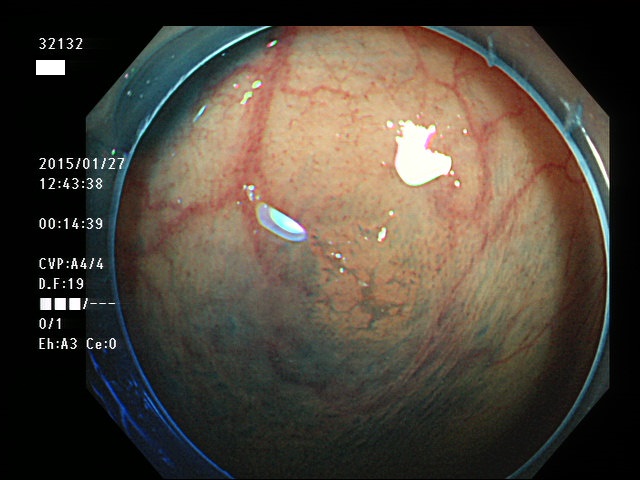

上記100名より抽出した平坦・陥凹型腺腫(=癌化の危険が高いが見落としやすい病変)の内視鏡写真

32101 32103 32105 32107 32108 32109 32110 32113 32114 32115 32116 32118 32119 32121 32123 32126 32129 32131 32132 32133 32134 32135 32138 32140 32141 32142 32143 32146 32147 32149 32150 32151 32152 32153 32154 32155 32156 32159 32160 32161 32163 32164 32167 32168 32173 32175 32176 32178 32183 32185 32187 32189 32190 32191 32194 32195 ・・・・の56名